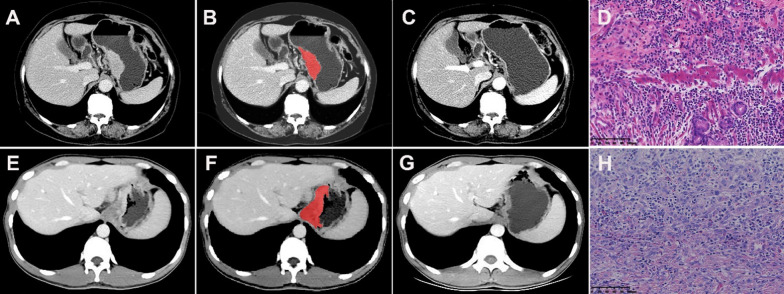

The CT images in arterial and venous phases were isotropically resampled by using trilinear interpolation in Artificial Intelligence Kit software (A. K, version: 3.3.0. R, GE Healthcare, USA) with a voxel size of 1 × 1 × 1 mm to minimize the effect of different scanning protocols or equipment on the radiomics features [29]. Region of interest (ROI) segmentation was performed by delineating around the tumor outline for the largest cross-sectional area in the CT axial plane (Fig. 1). Care was taken to avoid the gastric cavity and stomach contents, fatty tissue around the stomach wall and blood vessels when segmenting. Each ROI was outlined by a radiologist (L.C. 6 years of experience in abdominal imaging diagnosis) and supervised by a radiologist (Z.H., 8 years of experience in abdominal imaging diagnosis). To ensure the reliability and reproducibility of the radiomics features, 30 patients were randomly selected for their data to be segmented. For an analysis of interobserver agreement, a radiologist (L. CC) conducted the first-time whole-dataset segmentation, and another radiologist (H.W., 7 years of experience in abdominal imaging diagnosis) who was supervised by a radiologist (L.L., 9 years of experience in abdominal imaging diagnosis) delineated the images of the 30 selected patients during the same period. For analysis of intraobserver agreement, the radiologist (L. CC) repeatedly conducted segmentation 1 month after the first delineation.

Fig. 1.

Hypofractionated adenocarcinoma of the esophagogastric junction (AEG) in a 63-year-old man. A CT venous phase axial image before neoadjuvant chemotherapy (NAC), Borrmann staging type I, thickest tumor diameter of 3.4 cm. B Schematic diagram of region of interest (ROI) segmentation on ITK-SNAP software. C CT venous phase axial image after NAC, lesion near disappearance, and insignificant gastric wall thickening. D Postoperative pathological images; fibrous tissue hyperplasia with chronic inflammatory cell infiltration was seen; no tumor cells remained; and tumor regression was obvious (HE × 200). Hypofractionated AEG in a 36 years old man. E CT venous phase axial image before neoadjuvant chemotherapy (NAC), Borrmann staging type III, thickest tumor diameter of 3.2 cm. F Schematic diagram of region of interest (ROI) segmentation on ITK-SNAP software. G CT venous phase axial image after NAC, significantly smaller lesions with reduced enhancement. H Postoperative pathological images showed more chronic inflammatory cell infiltration in the mucosal and lamina propria layers with focal fibrosis (HE × 200)